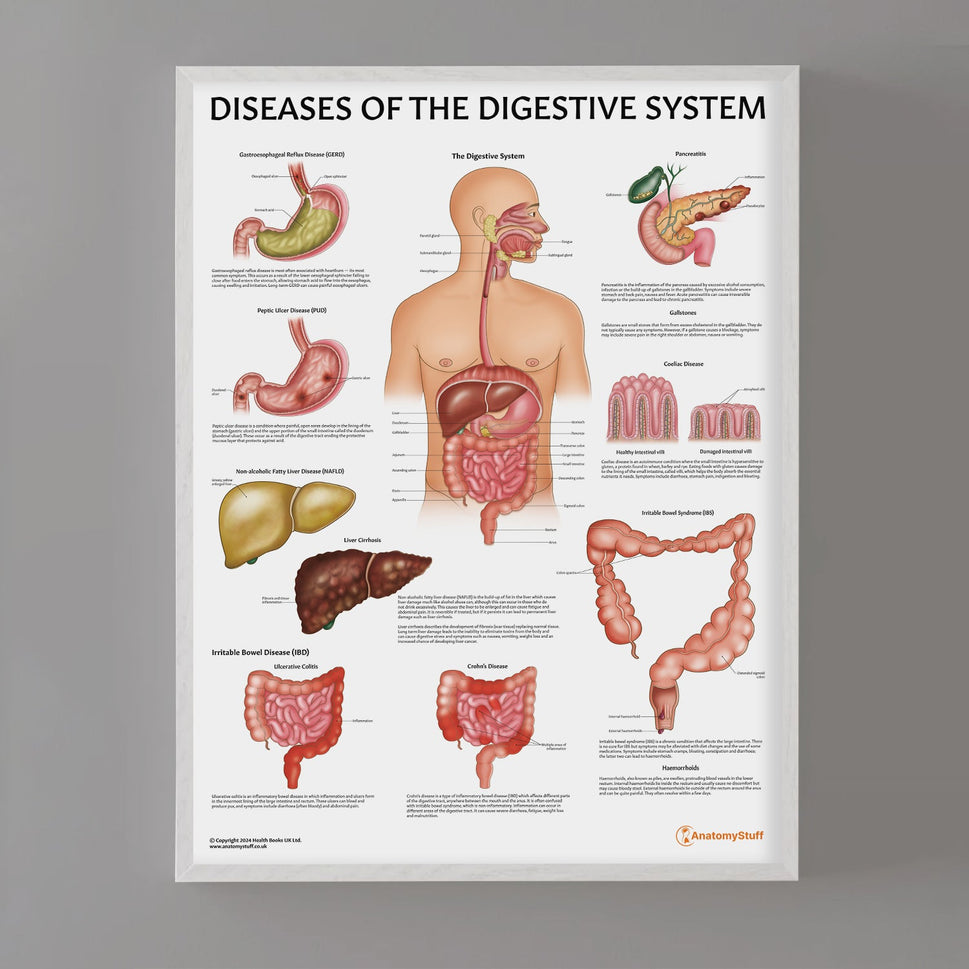

Enhance medical education with our collection of digestive system anatomical models including the stomach, liver, gallbladder, pancreas & colon models. Discover the anatomy of healthy organs as well as common gastrointestinal diseases such as stomach ulcers, gallstones and liver cirrhosis. Our digestive system anatomy posters are ideal for study and patient education.

At AnatomyStuff we stock a diverse range of digestive system anatomical models to suit your training needs. From budget models and affordable medical education posters to highly advanced 3D printed bowel models, you can transform medical training and patient education. As well as our own exclusive collection, we are proud resellers of 3B Scientific, Anatomy Lab, Denoyer-Geppert Science Company, ESP Models, Erler Zimmer and GPI Anatomicals. Explore our exclusive collection of digestive system anatomy charts, posters, fine art prints and digital anatomy study guides. Discover the anatomy of key organs like the liver, stomach, pancreas and bowel as well as the pathophysiology of common conditions like peptic ulcer disease, coeliac disease, IBD and much more. We have anatomy posters suitable for school children all the way up to medical degree level. From a liver anatomy poster to a digital study guide all about common GI disorders, find exactly what you need right here to enhance medical training and patient education.